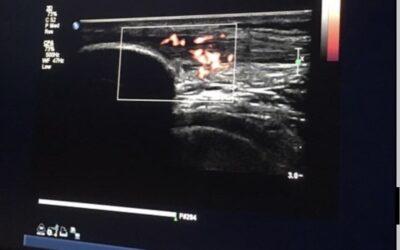

Observation is KEY with Palpation

Anterior Knee